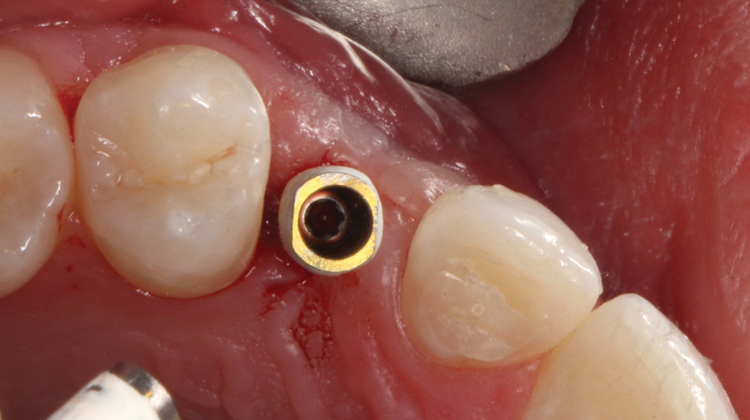

(46.) Occlusal view of the implant after placement.

Figure 46